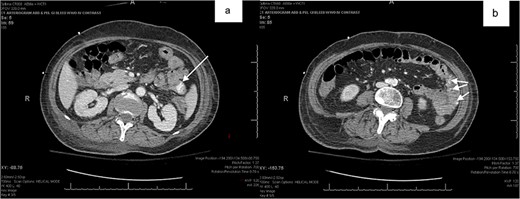

Patient 1 was a 70-year-old female with breast cancer (Grade 2 Intraductal Carcinoma) diagnosed in 2019, currently undergoing chemotherapy via a left chest port. She presented to the ER for a syncopal episode. She recently underwent port placement 2 weeks prior to presentation and received her first cycle of chemotherapy 5 days prior, which she did not tolerate well. She reported severe generalized weakness, joint pains and nausea since treatment, and one episode of emesis just before admission. Her hospital stay was complicated by declining renal function, melena and down trending hemoglobin, necessitating multiple transfusions of platelets and packed red blood cells (PRBCs). Esophagogastroduodenoscopy (EGD) showed an esophageal ulcer and gastroduodenitis, and colonoscopy revealed old blood in the terminal ileum without evidence of active bleeding or mucosal lesions. Despite a negative Meckel’s scan and mesenteric CT angiogram showing no evidence of mesenteric bleeding, her hemoglobin continued to decline to 5.3 on hospital day 20, at which time the patient received two units of PRBCs. Abdominal CT with oral contrast showed mild extravasation in the jejunal loop (Fig. 1a and b). A PE was then performed, which showed blood refluxing from the jejunum distal to the end of the scope, but no source was visualized. Another mesenteric angiogram was performed, which noted GI bleeding and she was transferred to the ICU to be stabilized.

(a,b) abdominal CT with oral contrast identifying extravasation in the jejunal loop.